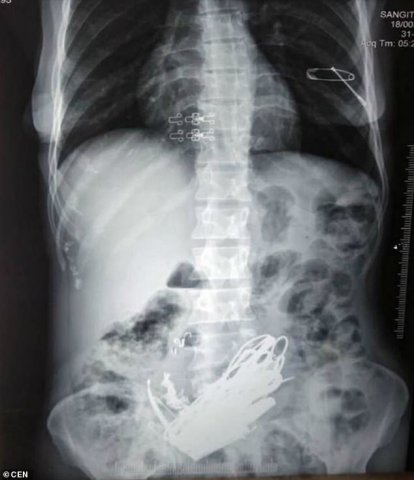

Xəstənin mədəsindən 1,5 kiloqram qayka, bolt və zinət əşyaları çıxarıldı - Fotolar

Tarix: 15-11-2018 17:18 | Bölmə: Cəmiyyət

Hindistanlı cərrahlar pasiyentin mədəsindən 1,5 kiloqram çəkisi olan qayka, bolt və zinət əşyaları çıxarıblar.

Reyting.az-ın məlumatına görə, əməliyyat 3 saat çəkib.

Sanqita adlı qadın (soyadı məlum deyil, yaşı 40-dan çoxdur) mədəsindəki ağıralara görə Ahmadabad's Civil Hospitala müraciət edib.

Onu rentgendən keçiriblər və bu zaman mədəsində böyük həcmdə metal ildırımları, milləri, mis üzük və hətta sancaq olduğu görünüb. Sacaqlardan biri hətta qadının ağ ciyərinə, digəri mədəsinə sancılıbmış.

Pasiyenti təcili əməliyyat ediblər. Onun mədəsindən ümumi çəkisi 1,5 kiloqram olan çox sayda metal əşya və zinət əşyaları çıxarılıb. Hazırda qadının vəziyyəti sabitdir.

Həkimlərin sözlərinə görə, qadın çox güman ki, akufaqiya adlanan nadir ruhi xəstəlikdən əziyyət çəkir. Bu cür xəstəliyə yoluxanlar metal əşyaları və digər yeyilməyən şeyləri yeməyə meylli olurlar.